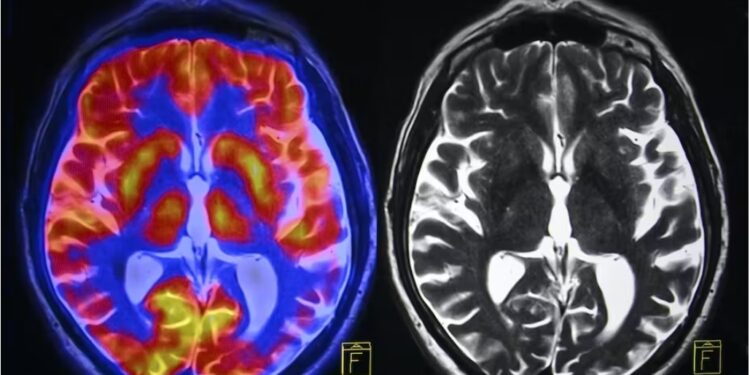

But the keywords in that last sentence are ‘after the stressful event is over’. Otherwise, excessive stress continuing over a period of time damages the brain. Prolonged stress slows down brain blood flow and causes plaques to form which narrow arteries and can even permanently damage them. When we are stressed muscles tense up, especially in the neck, which further reduces blood flow to the brain.

Chronic stress is a terrible thing for neurons. If stress levels rise for too long the brain is unable to participate in neurogenesis and worse, can begin to kill cells. Chronic stress also leads to the ageing of brain tissue and can affect the lifespan of neurons in a similar way to a concussion or the onset of a neuro-degenerative disorder. The remaining live brain cells are not particularly healthy either. Chronic stress causes neurons to become overactive. This can create new neural pathways over time which alters the way your brain works.

We can’t talk about stress without talking about the hormone which is largely responsible for these harmful effects: cortisol. Cortisol is produced when we experience stress of any type – both good and bad. A small amount of cortisol is not harmful and even has some positive effects. Excess cortisol has terrible effects on the body, from weight gain and sleep disturbances to a shrinking of the hippocampus, which interferes with the ability to concentrate and remember facts and circumstances. The hormone can increase the size and activity level of the amygdala which helps give memories emotional meaning. A more active amygdala can make us more sensitive to fear and anxiety.

Chronic stress has other effects as well. It can provoke the creation of more white matter, the fatty tissue which makes up half of the brain tissue where a lot of neural communication takes place.

Too much white matter means less room for grey matter – the place where the brain processes all physical, emotional and behavioural aspects. This imbalance can create emotional and cognitive problems that don’t go away when prolonged stress finally passes.